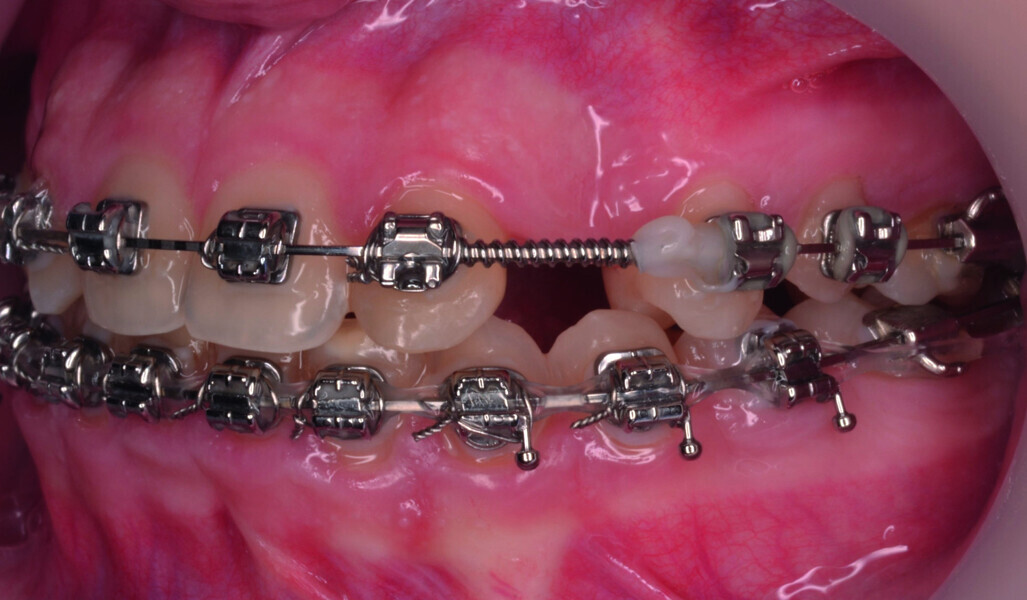

Orthodontic management of maxillary lateral incisors agenesis